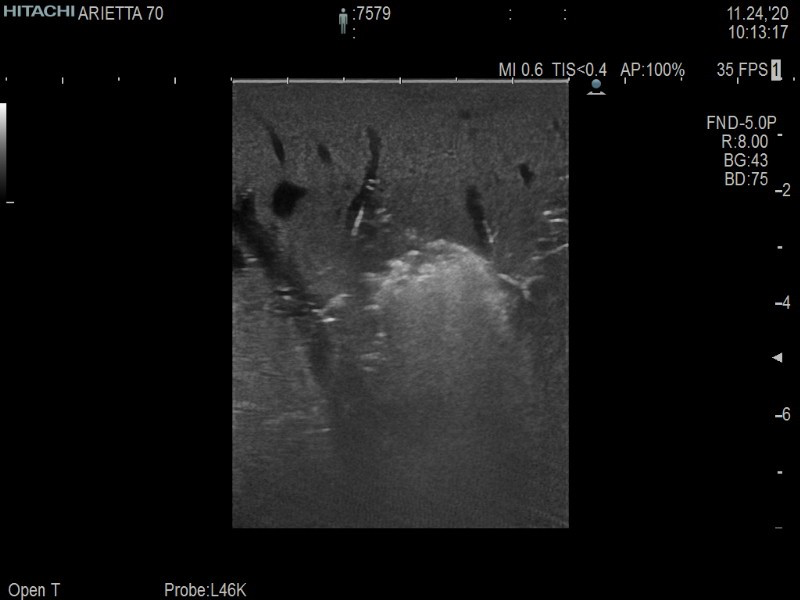

Arietta 70

Recognized for our outstanding image quality, outstanding system reliability and intuitive use of cutting edge technology, Fujifilm Healthcare remains the standard in the field of Surgery.

Learn moreArietta 70

Recognized for our outstanding image quality, outstanding system reliability and intuitive use of cutting edge technology, Fujifilm Healthcare remains the standard in the field of Surgery.

Imaging Clearly Defined

State-of-the-art digital architecture and advanced imaging features to redefine the capabilities of surgical ultrasound.